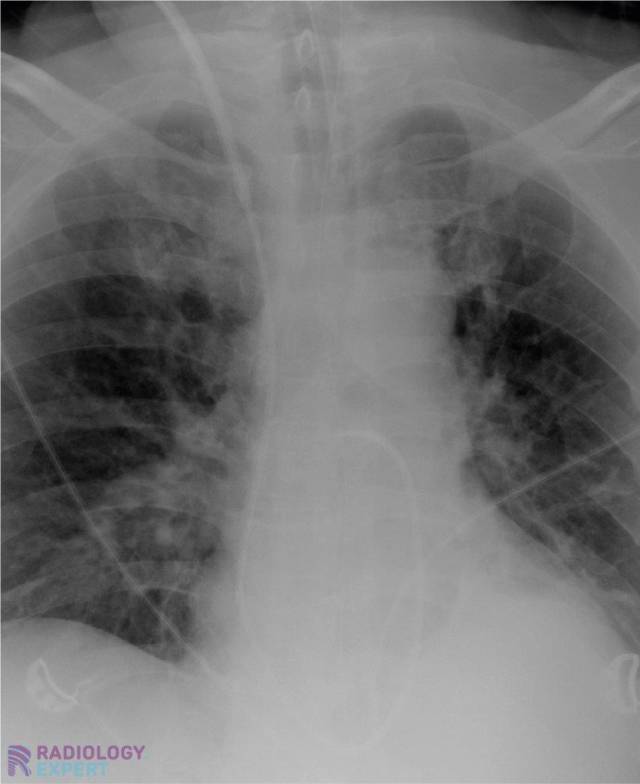

Swan-Ganz catheter in pulmonary artery Swan-Ganz catheter in pulmonary artery

Click image to see overlay